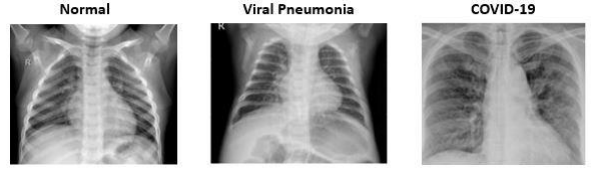

The sample images of Normal, Viral and COVID-19 patients are shown in figure below: